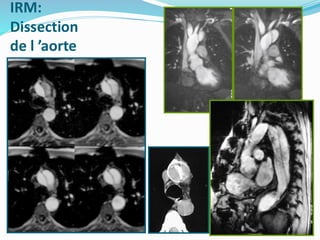

IRM:

Dissection

de l ’aorte